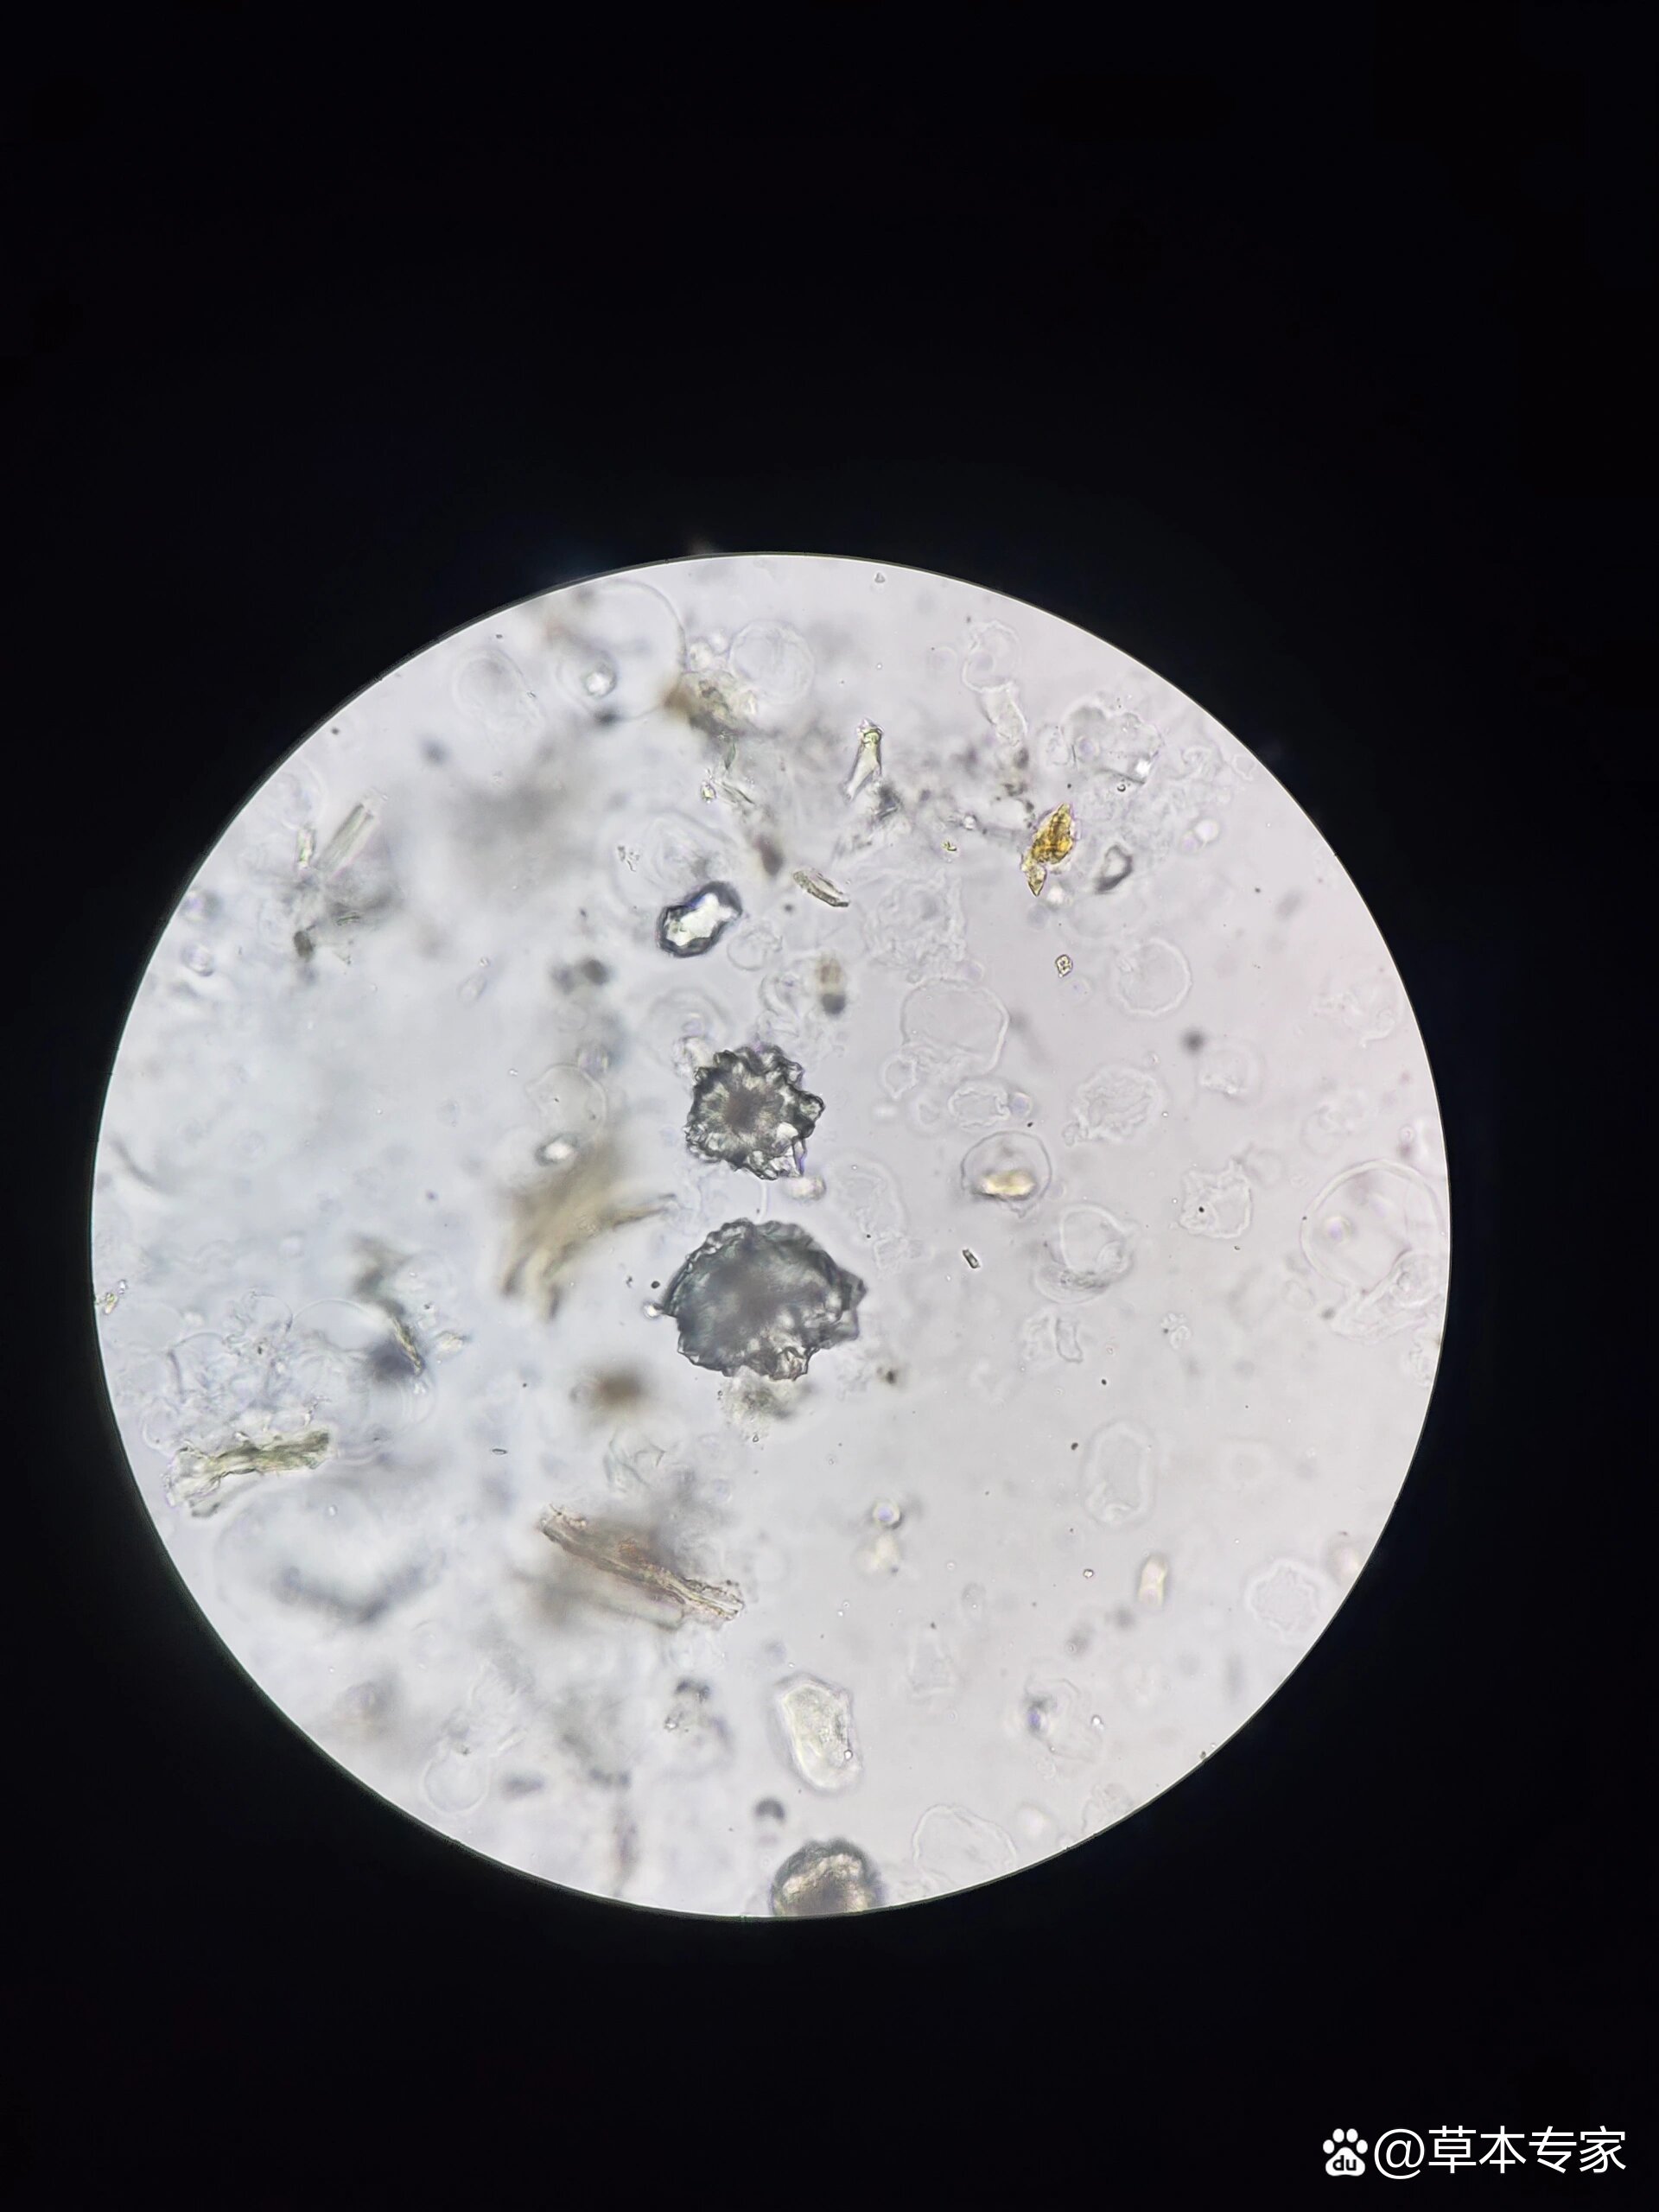

大黄粉末显微鉴别图 大黄粉末显微鉴别图 草酸钙簇晶:大而多.

大黄粉末显微图